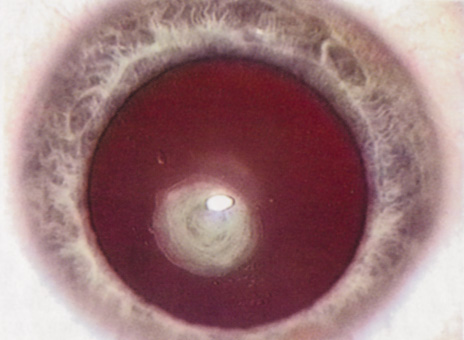

Physicians often order special tests to help determine a patient's visual potential. Some of these tests are acuity specific. These can be particularly helpful in guiding patients who may have comorbid ocular conditions. Some devices have been designed to project a Snellen chart through the clearest area of the cataractous lens to assess retinal acuity potential such as the potential acuity meter. Studies also have shown a good predictive value by checking vision with a brightly illuminated near card.53 Of course, this can be performed with no additional office equipment. Various other commercial devices, including interferometry and various different pinhole and illumination device combinations, are available.

These approaches are not possible for patients with mature cataracts. Some more general, nonspecific prognostic tests can be performed. If a patient is able to identify the colors of projected lights, this usually indicates that some cone-mediated macular function is present.

Blue field endoscopy also may indicate some macular function. This test is performed by projecting a blue light into the eye. The patient may report seeing small round specks moving around in the vision. These specks correspond to white blood cells passing through the perifoveal capillaries.

The Purkinje phenomenon is tested easily by rapidly wiggling a transilluminator directed toward the globe through the lower lid in a darkened room. If the patient reports a pattern of crooked lines or branches, then he or she is seeing the shadows cast by the retinal blood vessels, indicating that the posterior pole is attached and functioning to at least some degree. Although positive results from the test are encouraging, some patients may still have limited vision after surgery; similarly, some rare patients may test negatively on all these tests and still recover good vision.